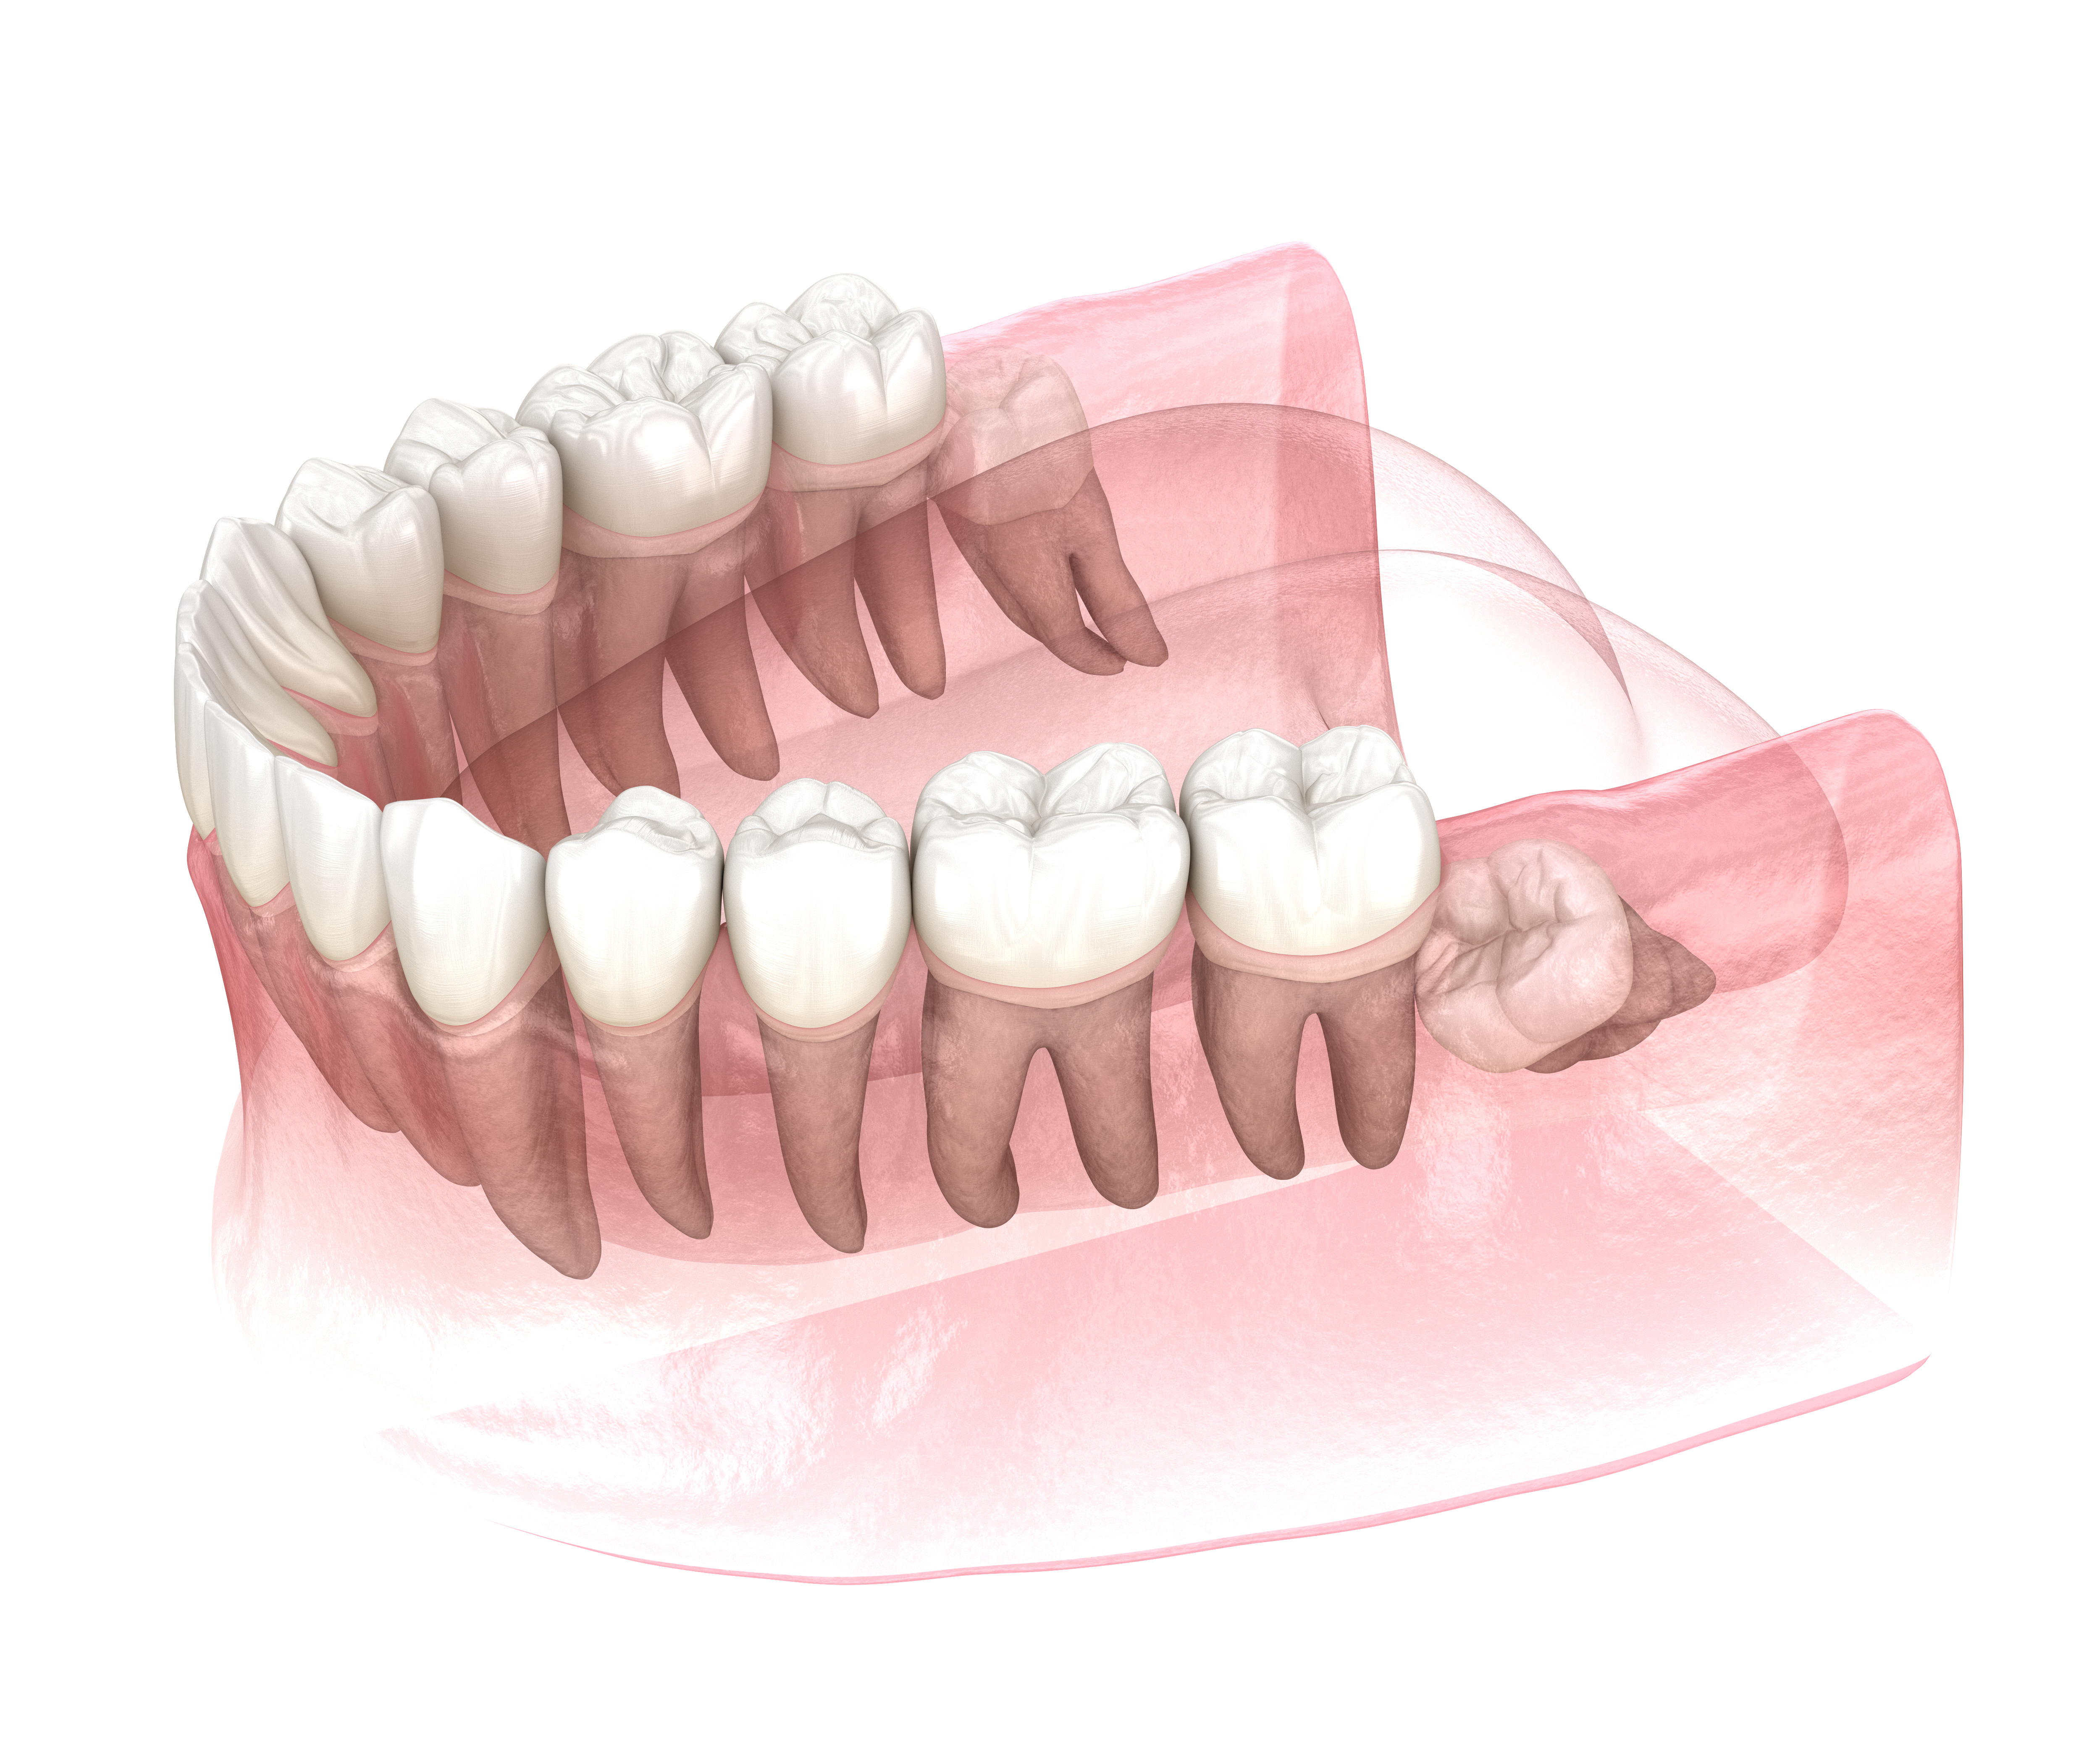

Дентальная галерея: ретинированный зуб клык и его лечение

Раздел: Компас решений